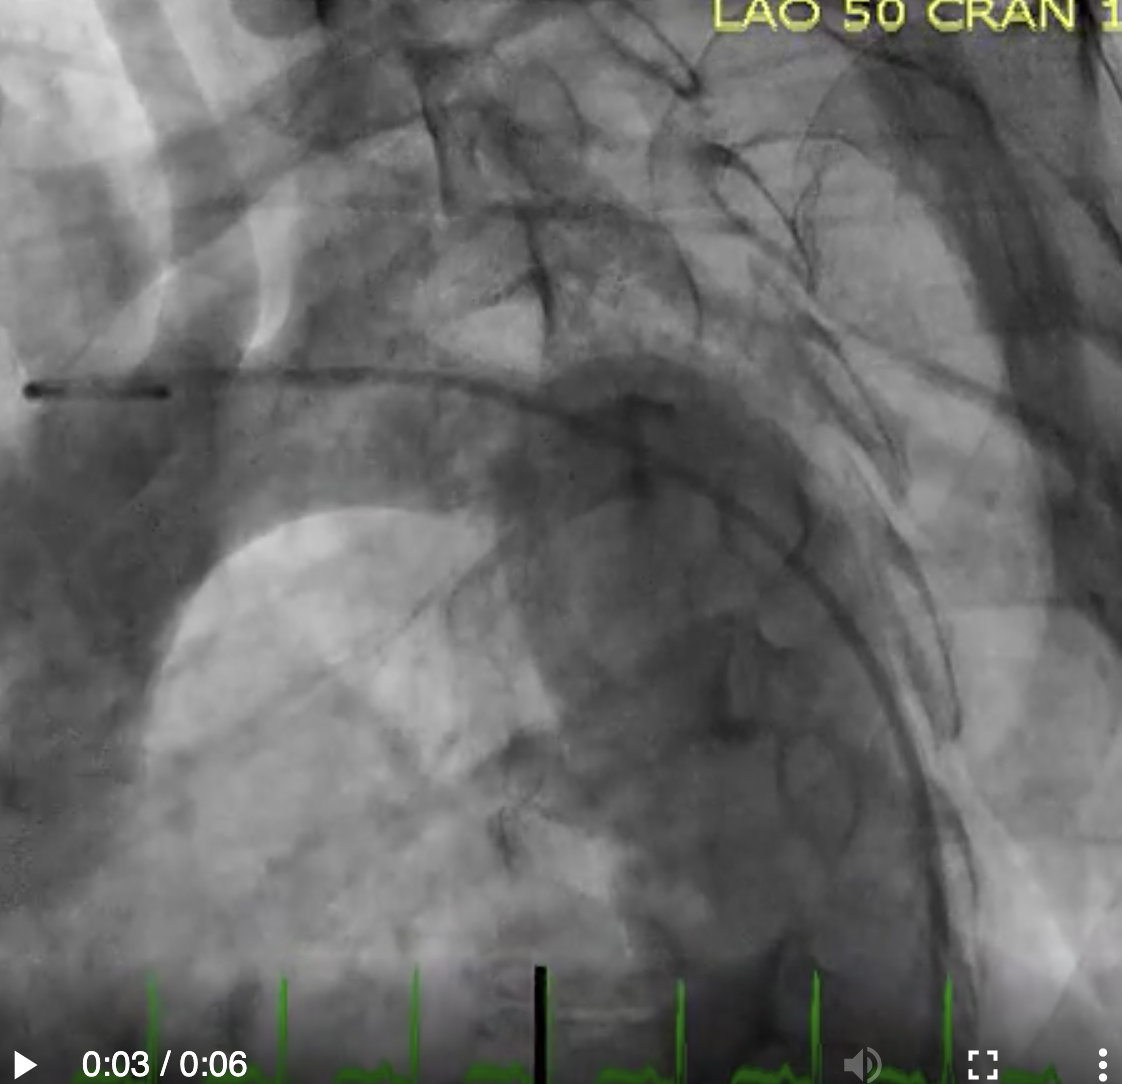

Describe the findings:

RCA dissection